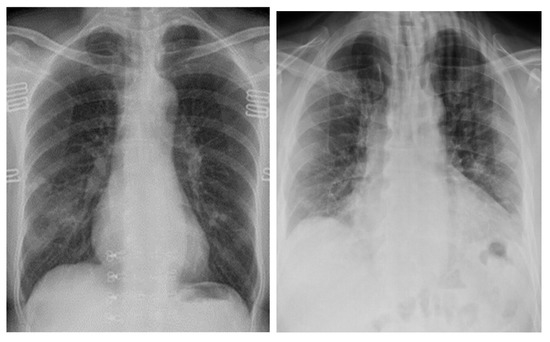

From Figure 5 below, we see that at 700 epochs, the images generated by the WGAN-GP model show high resemblance to chest X-ray images, but they are still pixelated. The WGAN-GP Generator and Critic Loss were trained with a dataset of 1000 images, and the WGAN-GP’s loss was stable, as it did not fluctuate randomly throughout the training.

Figure 5.

Generated COVID-19 positive chest X-ray images with dataset of 1000 images using WGAN-GP at 700 epochs.